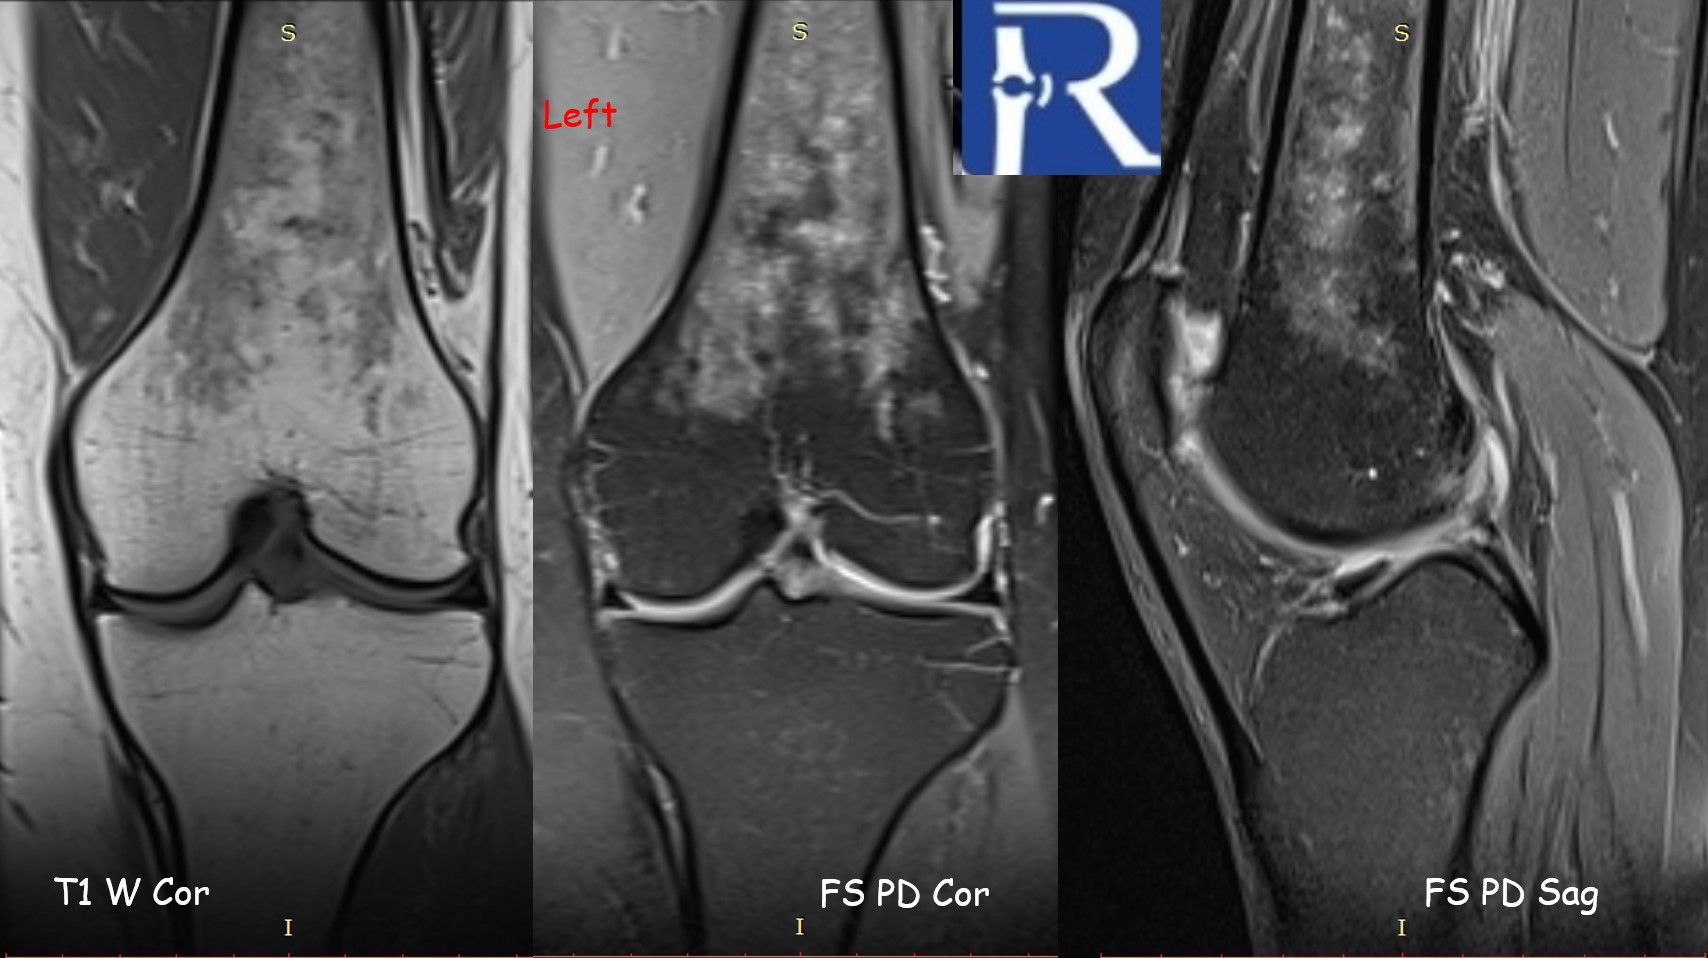

The Forgotten ACL Finding: Stump Entrapment Beyond the Tear in Pivot-Shift Injuries Clinical Context A 46-year-old male presented with acute ...

The arcuate sign is a fibular head avulsion fracture indicating posterolateral corner injury, commonly associated with ACL and PCL tears. Early recogn ...